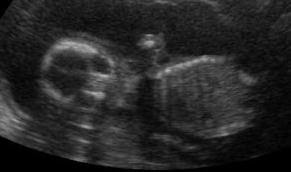

Look... She's waving at you!! You can't really tell but she'll knealing too.

The pictures that we got today weren't the best but we have another ultrasound scheduled for March 22nd and then the 4-D one is scheduled for April 24th. Woo hoo!!